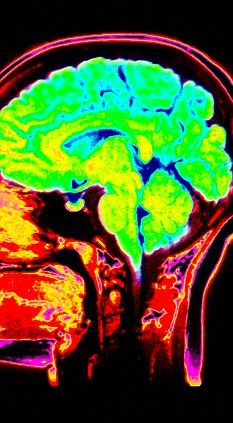

新浪科技讯 5月19日消息,据国外媒体19日报道,人类大脑有两个用来处理怀疑的独立部分,第二部分只在和不信任的人交往时“启动”,所扮演的角色类似于一个测谎仪。

首先,怀疑是情感。研究中,志愿者同磁共振成象(MRI)扫描仪相连。结果显示,他们脑中处理恐惧的区域表现得很活跃。随后,另一个用来处理记忆和识别的脑区域开始运作。看来是人类进化成疑心很重的生物了。专门用来处理怀疑的脑回路对早期人类可能十分重要。

美国弗吉尼亚理工大学卡里林恩研究所的科学家发现,怀疑存在于两个不同的大脑区域——杏仁核和海马旁回中,前者在处理恐惧和情绪记忆上扮演着主要角色,后者和记忆以及场景识别存在密切关系。

弗吉尼亚理工大学卡里林恩研究所计算精神病学中心和人类神经影像实验室主管瑞德-蒙塔古是这项研究的负责人,他说:“我们对人在简单的社会交往中是如何评估他人可信度的感到好奇。我们发现,杏仁核和怀疑的底线水平有密切联系。一个人根据情绪状态和眼下情况对其他人的可信度进行评估。但令我们感到吃惊的是,其他人的行为引起怀疑时,海马旁回就会启动,扮演了一个类似天生测谎仪的角色。”

这些科学家用功能性磁共振成像(FMRI)研究了怀疑的神经基础。75对参与者参加了60轮简单的讨价还价游戏,每对都有一个买家和一个卖主。与此同时,他们的大脑和扫描仪连接。每轮开始时,买家都会得知一个假设物件的实际价值,接着向卖主出示一个价格。然后卖主定价。如果卖主的价格低于假设物件的给定值,交易就会进行。卖主得到售价,买主则收到售价和实际价格间的任何差价。如果卖主的价格高于假设物件的实际价值,交易就会终止,双方都得不到现金。(杨孝文 任秋凌)